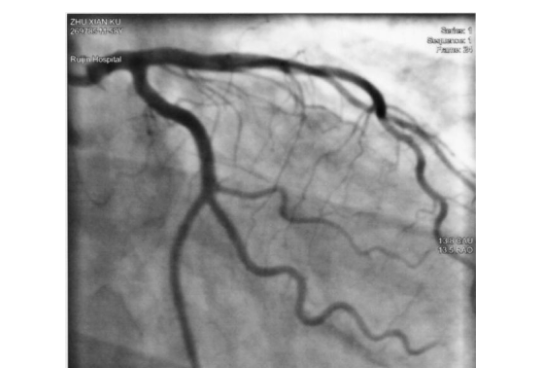

醫(yī)用微導(dǎo)管為醫(yī)生提供了準(zhǔn)確安全的診斷和治療手段。醫(yī)用微導(dǎo)管的應(yīng)用不僅提高了醫(yī)療的效果和安全性,也為患者提供了更好的治療體驗(yàn)和康復(fù)機(jī)會(huì)。隨著醫(yī)學(xué)技術(shù)的不斷進(jìn)步和創(chuàng)新,醫(yī)用微導(dǎo)管在未來將發(fā)揮更廣泛和重要的作用。1、介入領(lǐng)域介入醫(yī)學(xué)是通過微創(chuàng)手術(shù)技術(shù)在患者體內(nèi)進(jìn)行診斷和治療的一種方法。微導(dǎo)管作用在介入領(lǐng)域...

指引導(dǎo)絲生產(chǎn)廠家的產(chǎn)品采用高度不透射線的外殼材料,這意味著導(dǎo)絲在影像診斷過程中不會(huì)產(chǎn)生明顯的阻礙。這種特性使得醫(yī)療人員能夠更準(zhǔn)確地觀察患者的血管通路情況,從而提高手術(shù)的準(zhǔn)確性和安全性。1、特殊的親水聚合物薄層采用特殊的親水聚合物薄層涂覆技術(shù)。這一薄層能夠降低導(dǎo)絲與血液或組織的摩擦力,減少不必要的創(chuàng)傷...

指引導(dǎo)管生產(chǎn)廠家產(chǎn)品采用尖端防導(dǎo)絲切割設(shè)計(jì),能夠減小穿刺過程中對(duì)組織的損傷,這種創(chuàng)新的設(shè)計(jì)有助于減少術(shù)后疼痛和并發(fā)癥的發(fā)生。1、采用抗折鈦合金微導(dǎo)絲,插入順暢為了確保導(dǎo)絲的穩(wěn)定性和耐用性,指引導(dǎo)管生產(chǎn)廠家產(chǎn)品采用了高質(zhì)量的抗折鈦合金微導(dǎo)絲。這種材料具有出色的彎曲強(qiáng)度,可以經(jīng)受住復(fù)雜的解剖環(huán)境和導(dǎo)管操...